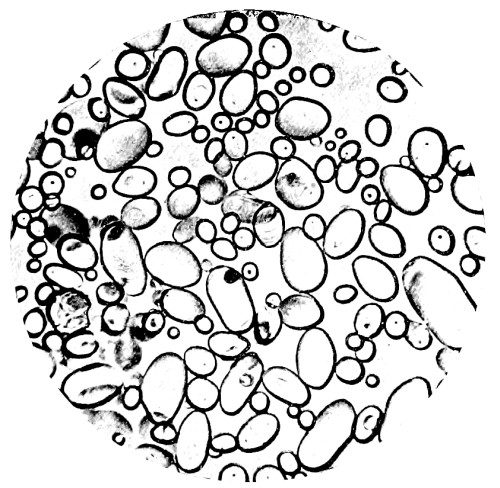

8. Measurement of Blood Corpuscles (human) 97

9. Measurement of Blood Corpuscles (sheep) 97

10. Photo-micrograph of Red Blood Corpuscles from Domestic Fowl 99

11. Photo-micrograph of Blood Corpuscles of Fish 99

12. Photo-micrograph of Blood Corpuscles from a Dried Stain of the Blood of a Cod-fish 100

13. Photo-micrograph of a Frog‘s Blood showing oval nucleated Red Corpuscles 101

14. Photo-micrograph of Crystals of Hæmin 102